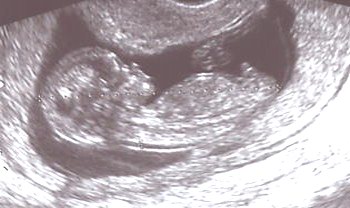

Hier sieht man einen Embryo der 13. SSW von

63 mm Länge.

Man erkennt den Kopf, die Nackenregion

und den Körper im Längsschnitt.

Die Nackenregion ist bei diesem Kind unauffällig.